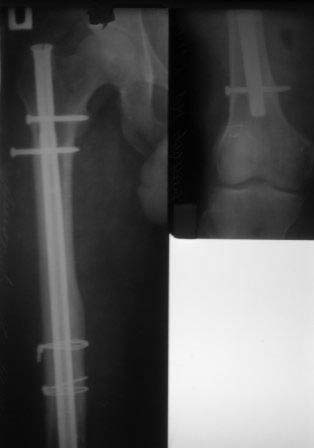

Уважаемые коллеги, обратился пациент1978г.р. , для удаления и/м стержня из правого бедра,

оперирован 2008году в городе Ангарск, Иркутской обл. Честно признаться я не знаю такого стержня, и как его удалить, кажется он еще сильно зажат в обл.истмуса, больной настаивает на удалении!

Это старый универсальный гвоздь Synthes.

Он самый. Стальной, полый расщепленный. Но если нет специального инструмента, то лучше не браться за это дело. Если в Ангарске ставили, скорее всего у них и инструмент для удаления есть. Лучше всего отправить больного по месту первичной операции. Или пусть ищет клинику, где точно есть инструмент именно для удаления этой модели универсального штифта Synthes.